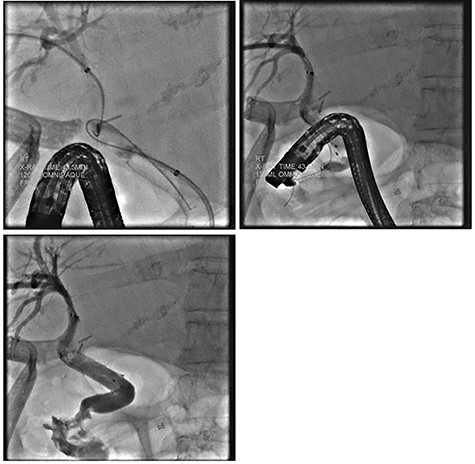

Repeat ERCP was performed and the CBD was easily traversed. Cholangiography demonstrated bile leakage within a well-developed sinus tract. A 10 x 80 mm fully covered metal Wallflex (Boston Scientific) stent was placed (Fig. 4).

ERCP demonstrating successful replacement of metal stent after explantation.